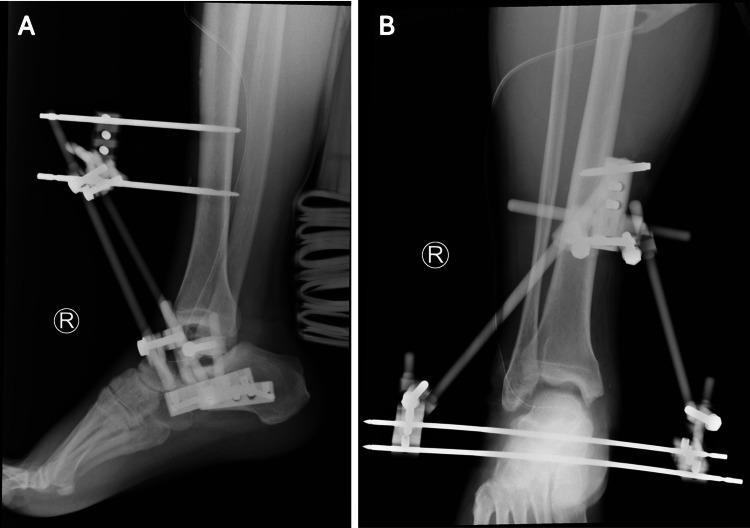

Post-traumatic missing talus is a rare and severe injury that often results in poor functional outcomes, with no consensus on the optimal treatment approach as strategies vary based on injury severity. We present the case of a 44-year-old male who sustained a missing talus following a high-energy motorcycle accident. After initial wound management and application of an external fixator, the patient underwent size-matched, fresh-frozen talus allograft transplantation combined with subtalar fusion. Postoperative radiography and CT confirmed successful transplantation with solid subtalar fusion, although progressive osteonecrosis was noted in the medial shoulder region of the talus. At the two-year follow-up, the patient exhibited limited ankle and hindfoot motion but was able to bear weight and walk without assistance, reporting no pain in his feet and achieving a final American Orthopaedic Foot & Ankle Society hindfoot score of 72. This case underscores the potential of total talar allograft transplantation with subtalar arthrodesis in treating severe talar bone loss or missing talus, although long-term follow-up is necessary to assess the clinical implications of medial talar collapse and the possible need for revision surgery.

创伤后距骨缺失是一种罕见且严重的损伤,常导致功能预后不良,由于治疗策略因损伤严重程度而异,目前对于最佳治疗方法尚无共识。我们报告一例44岁男性患者,在一次高能摩托车事故后发生距骨缺失。在进行初步伤口处理并应用外固定器后,患者接受了尺寸匹配的新鲜冷冻距骨同种异体移植联合距下关节融合术。术后X线和CT证实移植成功且距下关节牢固融合,尽管在距骨内侧肩部区域发现了进行性骨坏死。在两年的随访中,患者踝关节和后足活动受限,但能够负重行走且无需辅助,自述足部无疼痛,最终美国矫形足踝协会后足评分为72分。该病例强调了距骨同种异体全移植联合距下关节融合术在治疗严重距骨骨质流失或距骨缺失方面的潜力,尽管需要长期随访以评估距骨内侧塌陷的临床影响以及可能的翻修手术需求。